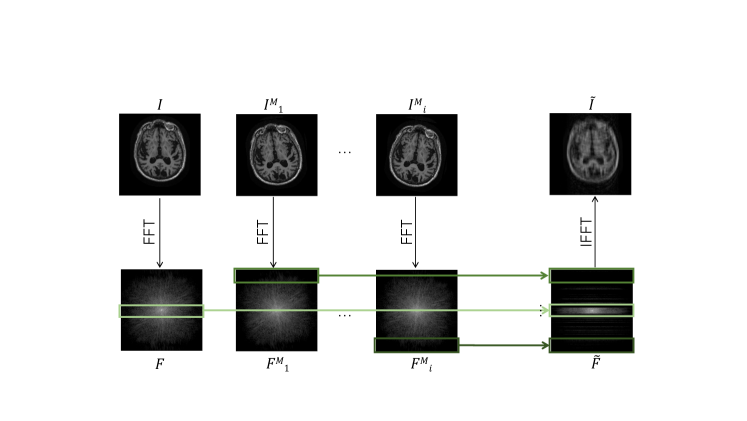

2 Joint Networks

MRI acquires Fourier transform measurements, referred to as k-space data. We assume a 2D multislice MRI acquisition. For each slice in this setup, the goal of image reconstruction is to generate an image from the acquired Fourier transform measurements . Classically, this reconstruction is computed via a 2D inverse Fourier transform, producing an estimated image . In practice, corrupted and possibly undersampled measurements are acquired instead of , and the goal is to estimate the desired image from the corrupted signal . Many strategies exist for selecting which measurements to acquire in frequency space. Here we consider Cartesian sampling, where measurement coordinates and are evenly sampled across the 2D Fourier plane, but our method can be generalized to other acquisition schemes. In this section, we define two neural network layer variants that combine image and frequency space convolutional features, referred to as Interleaved and Alternating, specify the network architectures, and describe the learning procedure.

We construct each joint network to contain 10 joint frequency and image space layers. We performed a hyperparameter sweep and observed that the accuracy of reconstruction on the validation set stopped improving for networks that included more than 10 joint layers. A single 2D convolutional layer acts on the frequency space output of the final joint layer to produce the final 2-channel complex output . The estimated image is the inverse Fourier transform of the network’s output, i.e., . All convolution blocks within both types of joint layers have kernel size 3x3 and 64 output features, resulting in a total of 670,622 parameters for the Interleaved network and 706,438 parameters for the Alternating network.